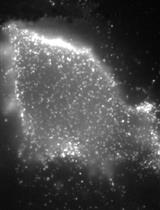

ELISpots Assay to Measure the Number of Murine Plasma Cells Producing Anti-dsDNA Antibodies

酶联免疫斑点法(ELISpot)检测产抗dsDNA抗体的鼠源浆细胞数量